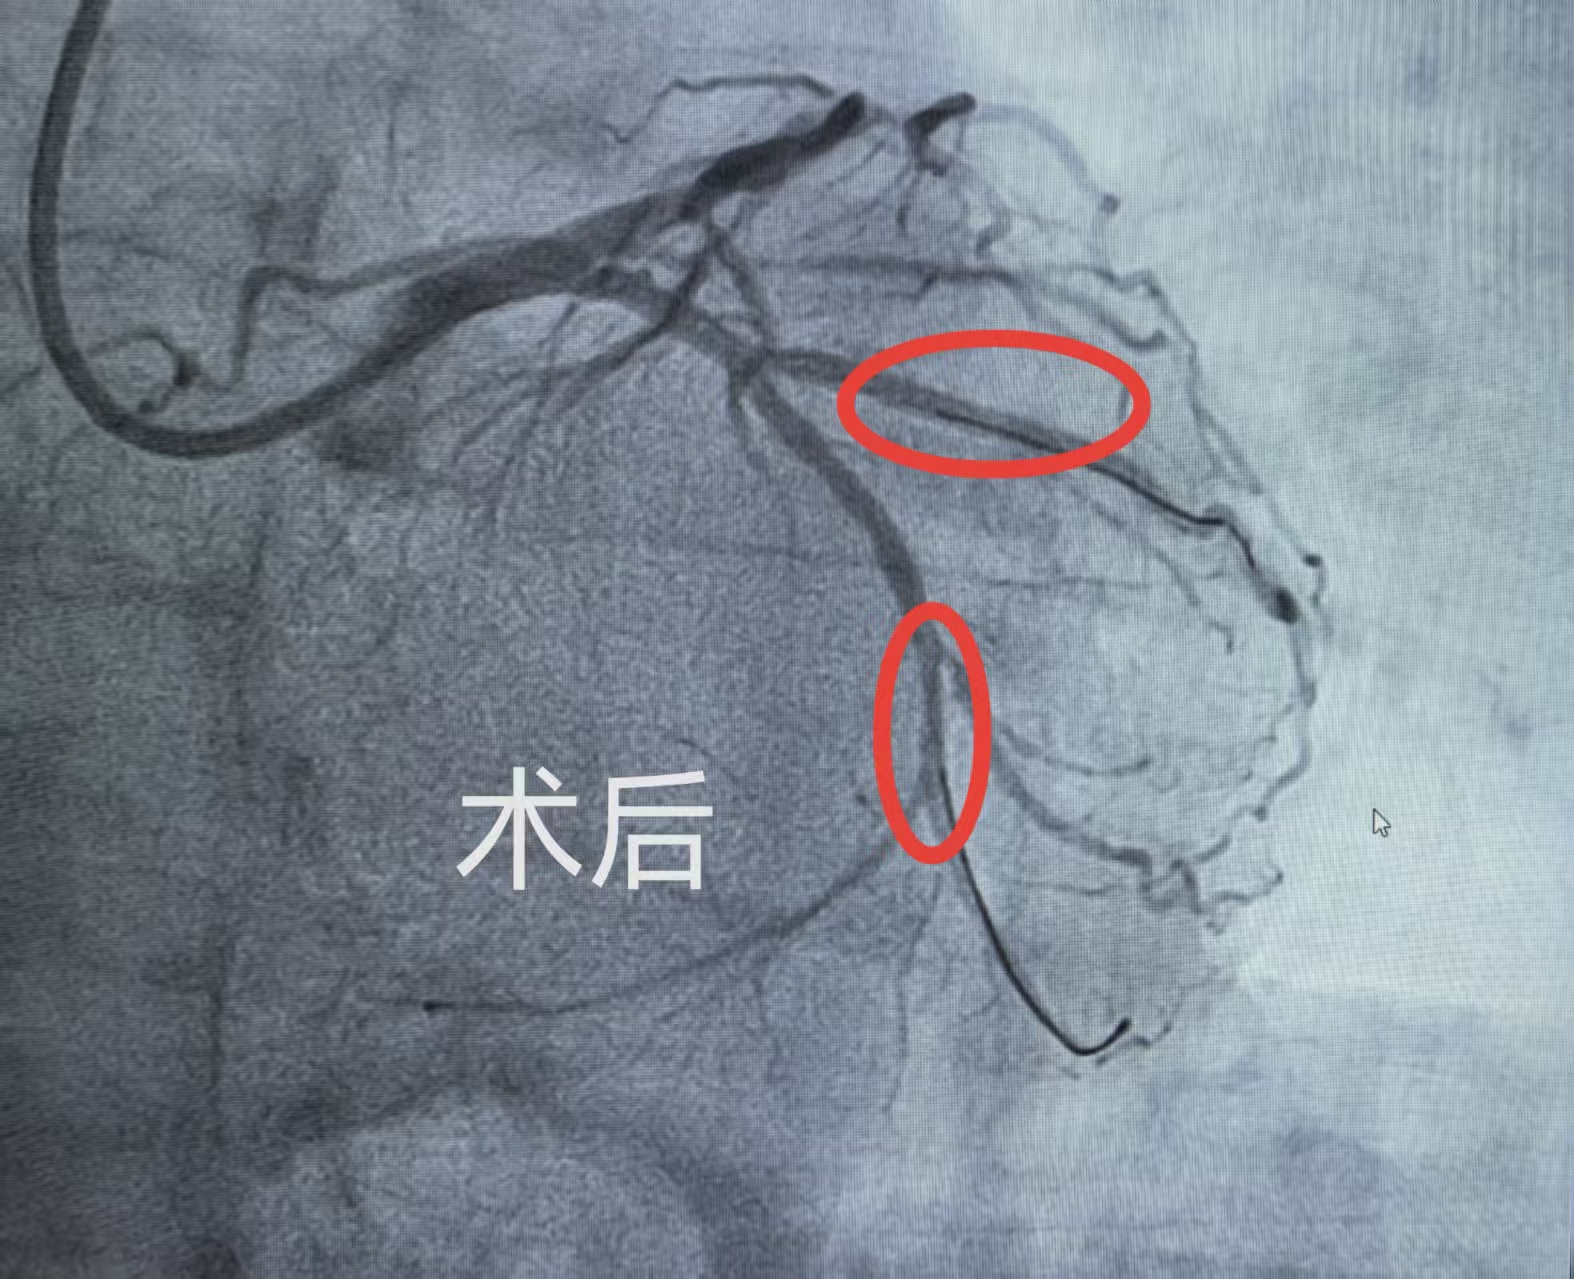

造影结果显示,陈阿姨心脏回旋支两支血管堵塞程度均高达90%,属重度狭窄,随时可能引发大面积心肌梗死。更棘手的是,其中一支堵塞血管旁伴有重要分支,常规支架置入易压迫分支血管,引发新风险。面对复杂的病变,牛锋主任团队反复研讨,量身定制“支架+药物球囊”微创方案:主干血管精准置支架,快速打通阻塞通道;另一支血管用药物球囊治疗,借局部药物释放改善狭窄,同时避开分支血管,兼顾疗效与安全。手术全程微创无痛,团队凭借精湛技术有条不紊推进,术后陈阿姨胸闷症状当场消失,生命体征平稳。